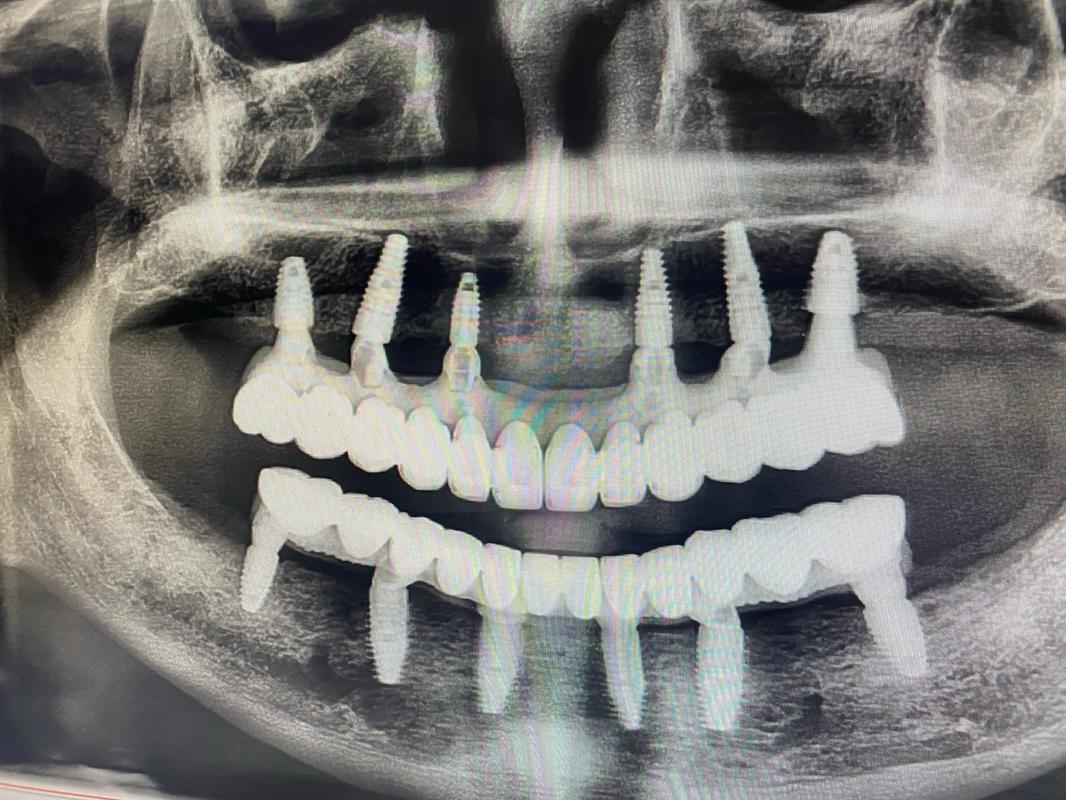

✅ 种植牙与自然牙无差异的微笑特写 - 科普对比类:

✅ 种植牙 vs 传统假牙的对比图(突出优势)

✅ 种植牙过程示意图(简化版,避免血腥)